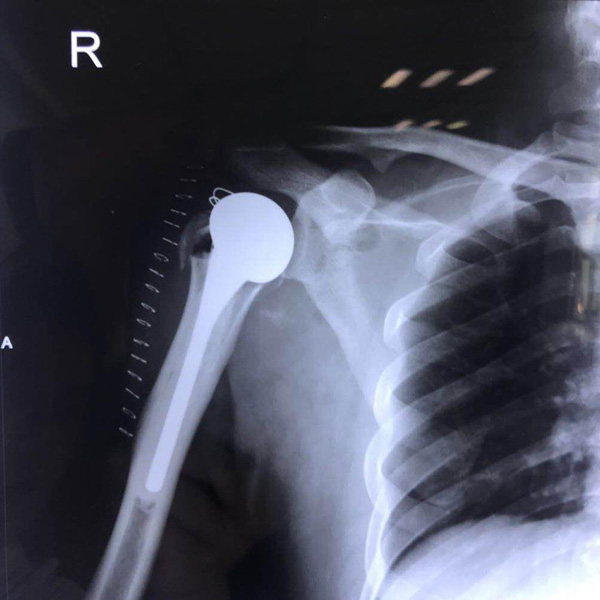

• 右側肱骨頭置換右側肱骨頭置換手術后手術前

右側肱骨頭置換

患者郭某,男,40歲,因嚴重車禍導致“右肱骨頭粉碎性骨折”,一般的手術很難將粉碎的骨折塊拼接起來,即便大致的拼接起來,因為骨面的不平......

在線咨詢+更多詳情+